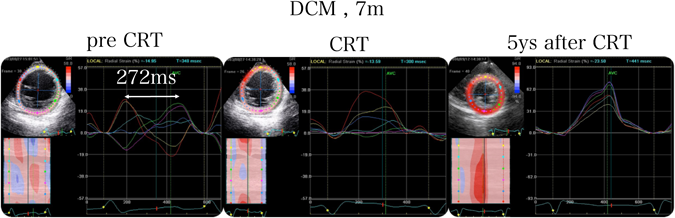

小児期のDCMや術後先天性心疾患症例では,アプローチの問題からCRT植え込みには心外膜リードが選択されることが多い.我々は,MRIのLGEで心筋viabilityの有無を判断した後,実際に術中にリードポジションを変えながら壁運動変化をリアルタイムに心エコーで観察し,septal flushやapexの左右へのrotationが最も改善する部位にリード位置を固定している.同時に,血圧,大動脈弁位でのvelocity time integral,心電図のQRS幅も計測して判断の補助とする.Fig. 10は,7ヶ月のDCM症例で,CRT施行前の中隔と後壁のRSではtime to peakが272 msの差があるのがわかる.スペックルトラックで検出した最遅延部位の近傍をさらに丁寧にリードポジションを変えて術中ガイドの心エコーをしながらCRTを施行したところ,CRT前から直後,長期の経過で著明に左室同期および収縮能が改善,正常化した.この症例は,NYHA class VIでカテコラミン離脱できなかった重症例であったが,至適ペーシング位置の挿入が心機能改善に大きく寄与していることを示唆していた.

Fig. 10 Speckle tracking echocardiography before and after cardiac resynchronizing therapy in infant dilated cardiomyopathy

In a DCM patient of 7 months, the difference between time-to-peak septal and posterior RS in the LV was 272 ms. During CRT, the optimal pacing site was located by changing the LV pacing position simultaneously. Echocardiography showed a serial and remarkable improvement of LV contraction, both immediately and 5 years after CRT. Moreover, the LV mechanical dyssynchrony was also recovered in time-to-peak RS curves by STE. CRT: cardiac resynchronizing therapy, DCM: dilated cardiomyopathy, LV: left ventricle, RS: radial strain, STE: speckle tracking echocardiography.